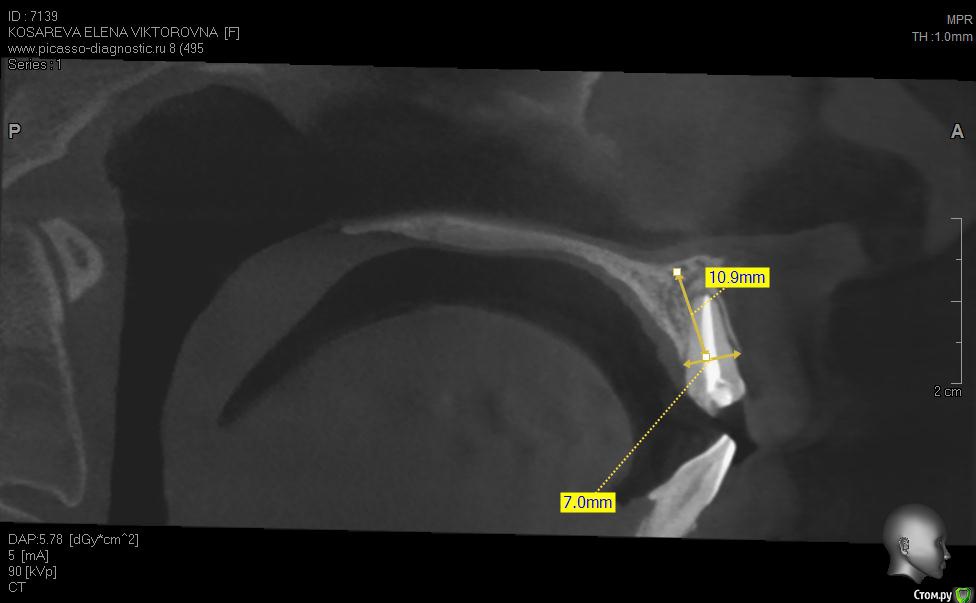

Уважаемые коллеги помогите пож с планом лечения, хотелось бы услышать ваши планы лечения,

пациент хочет красивую улыбку и импланты, клыки трогать категорически отказалась как опоры под временные на период интеграции имплантов